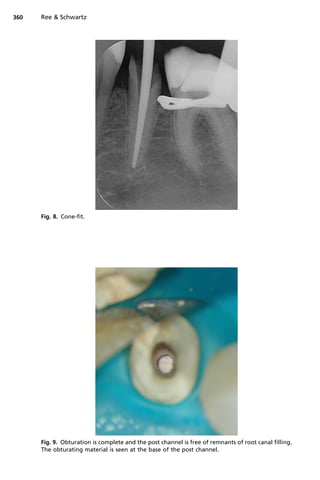

Fig. 8. Cone-fit.

1. Isolate the tooth with rubber dam and carry out root canal treatment (Figs. 7 and 8).

micro-brushes with alcohol (Fig. 9).